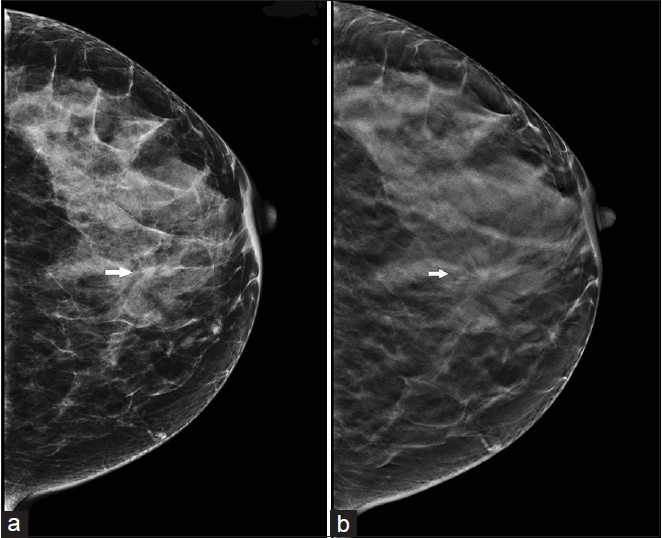

ئەگەر سىز ئوز ئوزىڭىزنى تەكشۇرۇش ئارقىلىق، ئەمچىكىڭىزدىن ھەرقانداق گۇمانلىق ئۆسمىنى بايقىسىڭىز، دەرھال دوختۇرغا كۆرۇنۇڭ. دوختۇر سىزگە مۇناسىۋەتلىك تەكشۇرۇشلەرنى ئىلىپ بارىدۇ. ئۇ تەكشۈرۈلار ئىچىدە ئادەمگە ئالاھىدا زەخمە ئەكەلمەيدىغان ھەم نەتىجىسى بىر ئاز توغۇرا بولغان تەكشۈرۈش ئىنگىلىزچە مەموگىرام دەپ ئاتىلىدۇ.

ئىسىڭىزدە بولسۇن، ئەمچەك راكىغا ئەڭ ئاخىرقى دىياگۇنۇز قويۇشنىڭ ئۇسۇلى ئەمچەكتىن توقۇلما ئىلىپ تەكشۈرۈش بولۇپ، ئۇ ئادەتتە زەخمىلىك تەكشۈرۈش ھىساپلىنىدۇ. دوختۇر ئادەتتە چوڭ يىڭنە بىلەن ياكى كىچىك ئوپىراتسىيە قىلىش ئارقىلىق ئەمچەك ئۆسمىسىدىن ئاز مىقتاردا توقۇلما ئىلىپ، ئۇنى مىكراسكوپ ئاستىدا تەكشۈرۈش ئارقىلىق راك ھۈجەيلىرىنى تاپىدۇ. شۇ ئارقىلىق ئەڭ ئاخىرقى دىياگۇنۇزنى قويۇدۇ.